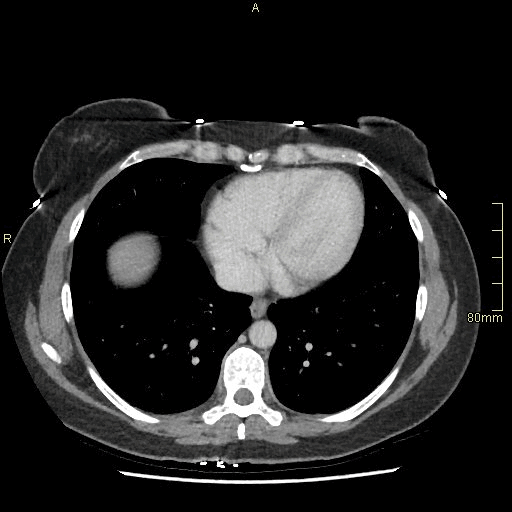

For patients over the age of 40, a non contrast KUB, and seperate nephrogenic and excretory (delayed) phases will be performed. For all patients under the age of 40, a non contrast KUB and a COMBINED dual nephrogenic/excretory phase will be performed. Image examples of this can be seen below.

Over 40 Years of Age

CT Urogram- Nephrogenic Phase (Axial)

CT Urogram- Excretory Phase (Axial)